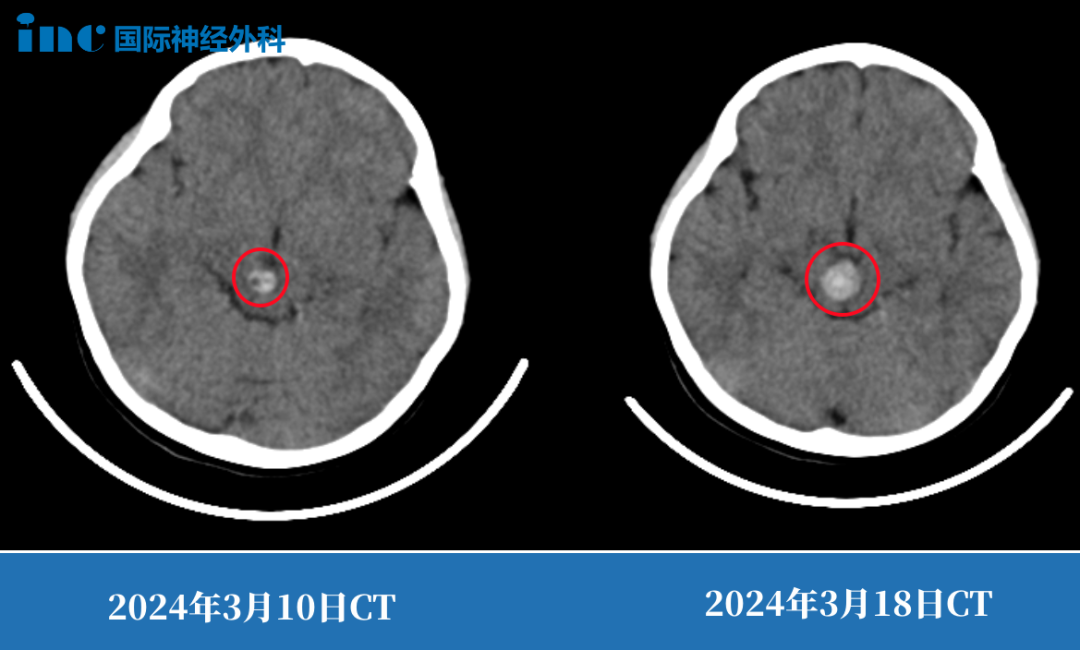

第二次出血,意味着病情的恶化,这一点在前后仅间隔8天的CT上就足以说明。